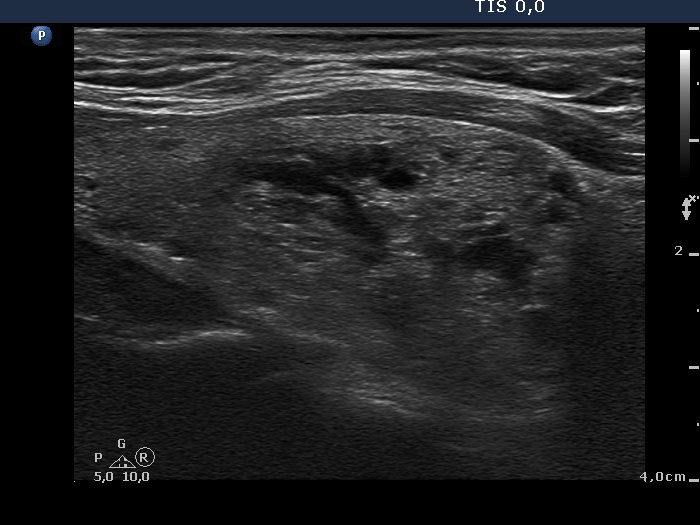

Ultrasonography: the thyroid was echonormal. There were two mixed nodules in the thyroid, one larger in the right and another smaller one in the left lobe. The vascular type of the nodules were not specific, they did not presented a halo.

After aspirating 7 mL brown fluid from the right nodule, the lesion presented a type 2 vascular pattern.